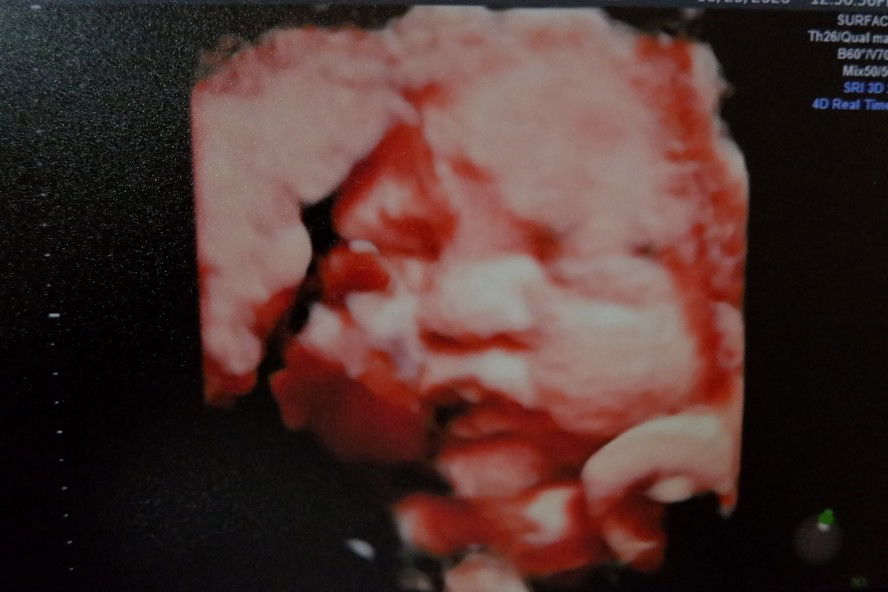

25weeks na!!

Moms,normal ba na may day and hours na tahimik at behave c baby? Kaunting movement lang ? May doppler ako sa bahay to monitor naman. Tnx #apasmommy